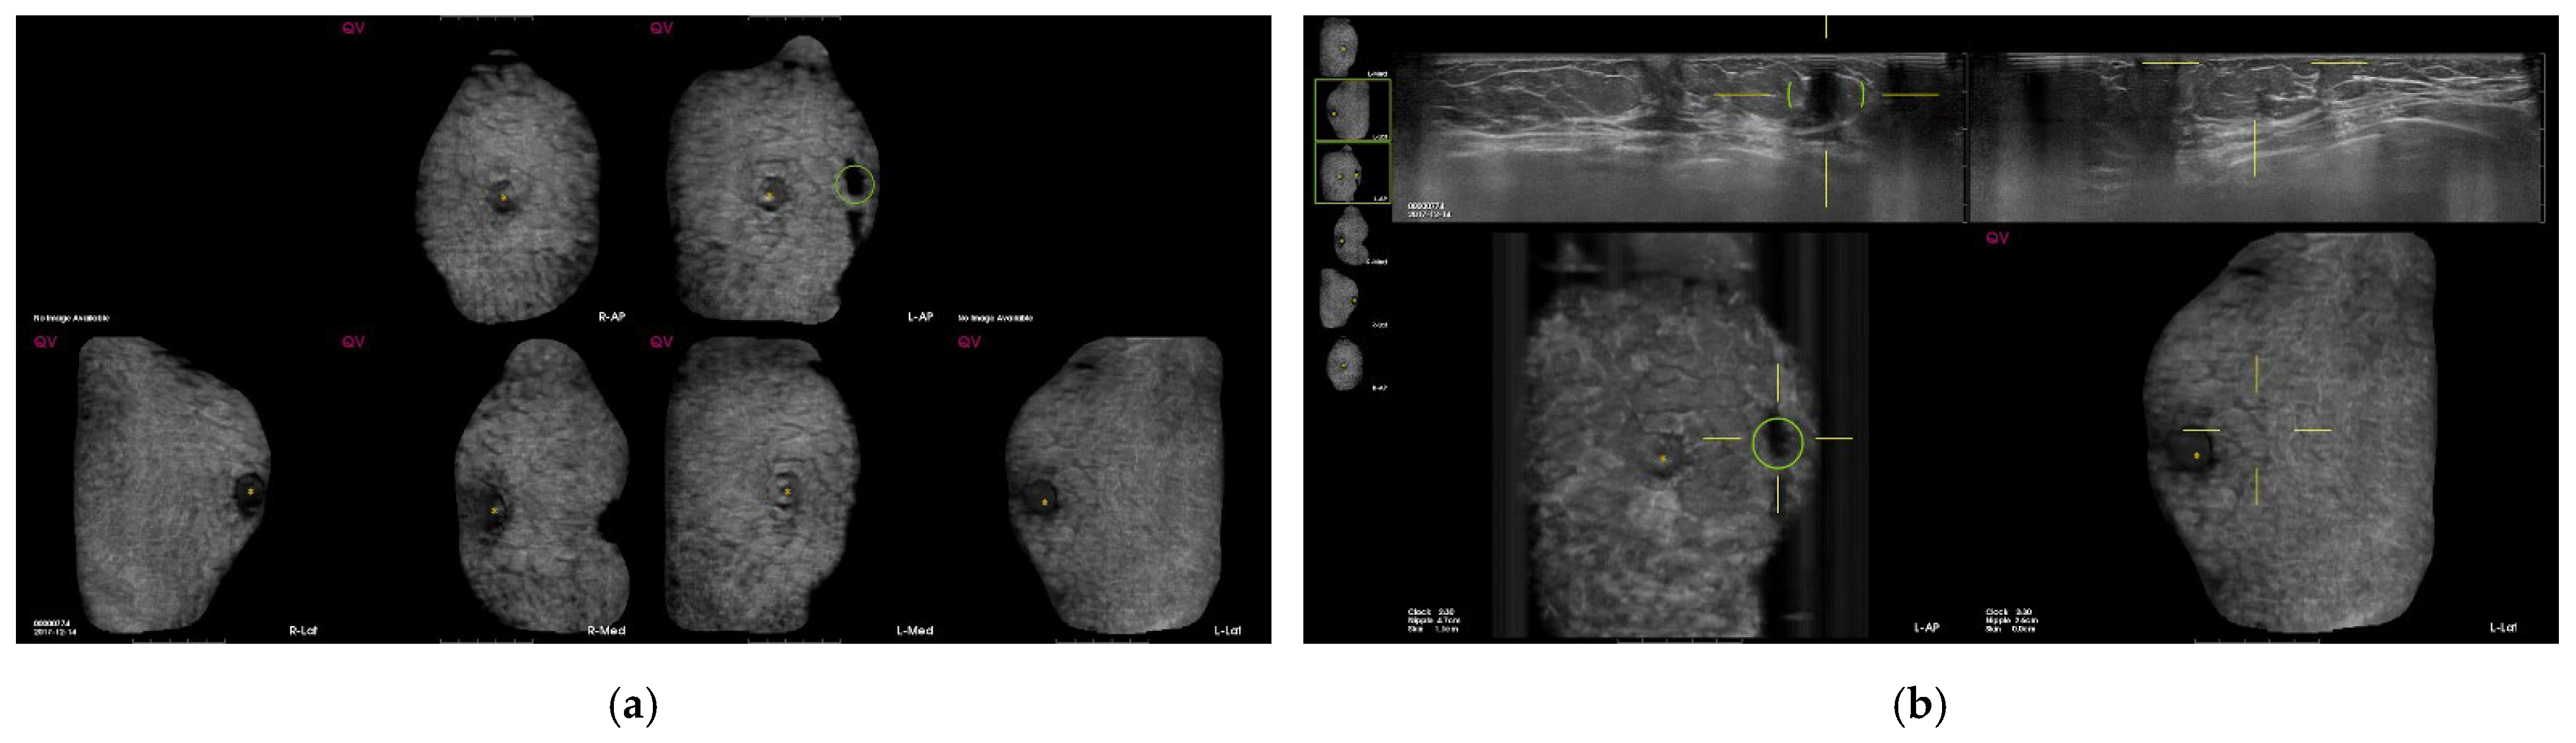

| Characteristics of CAD marks per lesion (n = 534) | n | % |

| Suspicious | 4 | 0.8 |

| Benign | 71 | 13.3 |

| Fat | 35 | 6.6 |

| Benign mass | 19 | 3.6 |

| Cyst | 9 | 1.7 |

| Fibrosis/heterogenous parenchyma | 8 | 1.5 |

| False-positive marks for pseudolesions | 459 | 86 |

| Marginal shadowing | 209 | 39.1 |

| Cooper’s ligament shadowing | 143 | 26.8 |

| Periareolar shadowing | 64 | 12 |

| Rib | 37 | 6.9 |

| Skin lesion | 6 | 1.1 |